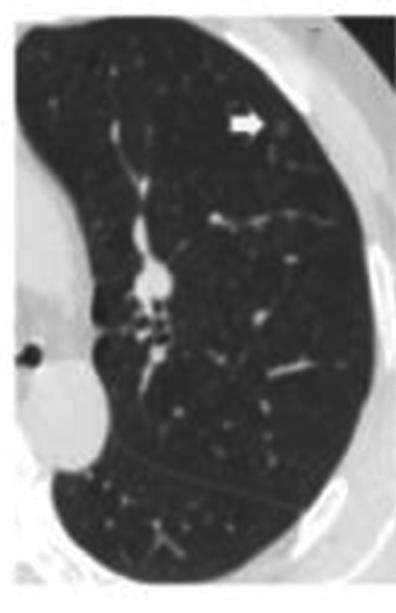

• 纯磨玻璃结节肺腺癌CT征象与其浸润程度的相关性分析及预测模型构建

2023, 48(4):423-429. DOI: 10.13406/j.cnki.cyxb.003200

摘要 (138) HTML (44) PDF 1.10 M (286) 评论 (0) 收藏

摘要:目的 探究纯磨玻璃结节(pure ground-glass nodule,pGGN)肺腺癌计算机断层扫描(computed tomography,CT)征象与其浸润程度的相关性,建立CT征象与浸润程度的预测模型。方法 回顾性分析424例经手术切除、病理活检证实且胸部CT表现为pGGN的肺腺癌患者临床资料及CT征象,根据病理活检结果分为非典型腺瘤样增生、原位腺癌、微浸润腺癌和浸润性腺癌4组,对组间差异采用卡方检验或Fisher确切概率法进行统计分析。对有统计学意义的结果,使用怀卡托智能分析环境(Waikato environment for knowledge analysis,WeKa)中的6种学习算法进行预测模型构建,并验证准确性,挑选出最适用于本研究的预测模型。结果 4组间在结节直径、结节密度值上的差异具有统计学意义(P<0.001),对应的直径平均值分别为6.90、8.65、10.71、14.56 mm,对应的密度平均值分别为-633.16、-543.04、-401.03、-322.94 HU,随着病灶的浸润程度加重,结节的直径及密度值呈现明显的上升趋势。4组间在结节边界、分叶、毛刺、血管穿行、胸膜凹陷、空气支气管征、空泡征等的差异具有统计学意义(P<0.05),而结节的生长位置,年龄、吸烟史、直系亲属肺癌家族史等差异无统计学意义(P>0.05)。随机森林算法所构建的模型预测准确率为76.42%~79.72%,Kappa系数为0.597~0.670,受试者工作特征(receiver operating characteristic,ROC)曲线下面积均大于0.9,在误差指标中表现最优,是最适合于本研究的预测模型。结论 pGGN的不同CT征象与其浸润程度密切相关,可以用于建立预测模型。基于随机森林算法所建模型,在有创干预前早期快速识别pGGN浸润程度的平均准确率为78.07%,准确度最高,对肺癌预测具有潜在应用价值。